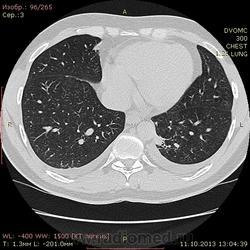

Пациент 35 лет. На УЗИ нашли житкость слева в плевральной полости, отправили на КТ - жидкость с обеих сторон. Из разговора с больным выяснилось, что около 1,5 месяцев назад была высокая тенпература, кашель - никуда не обращался и не лечился. На момент исследования ни на что не жалуется.

Похоже слева в S10? на поствоспалительные изменения? или на что похуже? И если на стороне поражения можно понять окуда жидкость, то справа - можно расценивать как реакция плевры на воспаление слева?

Локальный фиброз субсегмента S10 слева с бронхоэктазами. Двусторонний малый гидроторакс (толщина слоя жидкости до 1 см≈объём до 50 мл). Интересная субкапсульная ерундовина в S6 печени, наверное киста.